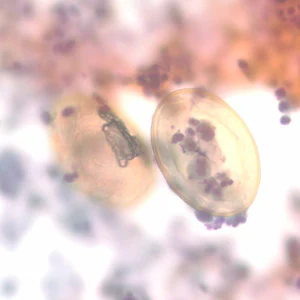

Eggs of Paragonimus spp. in unstained wet mounts.

Diagnosis is based on microscopic demonstration of eggs in stool or sputum, but these are not present until 2 to 3 months after infection. (Eggs are also occasionally encountered in effusion fluid or biopsy material.) Concentration techniques may be necessary in patients with light infections. Biopsy may allow diagnostic confirmation and species identification when an adult or developing fluke is recovered.